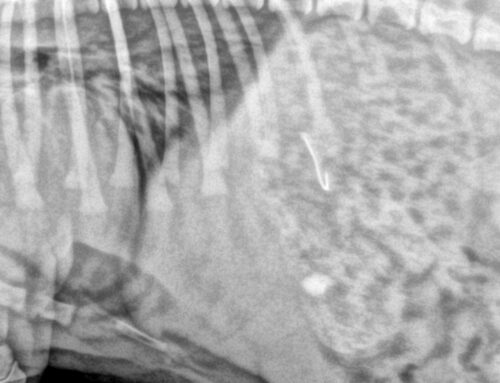

Decoracions, cintes, capses, llums i espelmes poden ser molt atractius per a gossos i gats, sobretot els més curiosos. Tanmateix, si es mosseguen o s’ingereixen, poden provocar des de bloquejos intestinals fins a cremades o electrocucions. La nostra recomanació és col·locar la decoració fora de l’abast, assegurant bé l’arbre de Nadal i evitant l’ús d’espelmes enceses a prop.